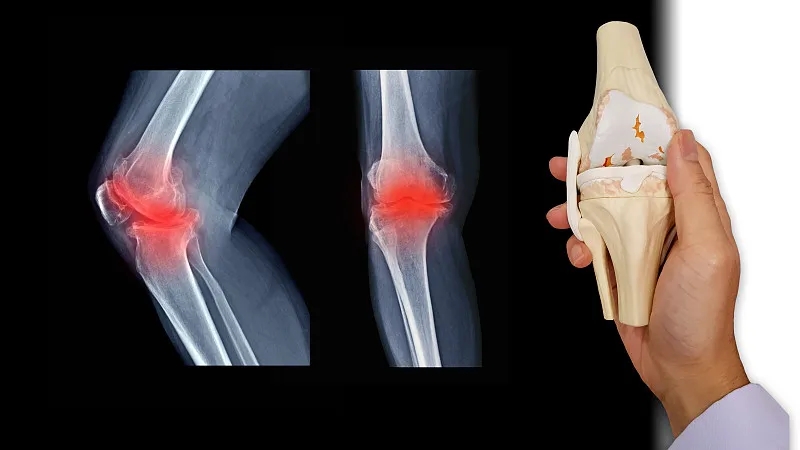

關節炎是一個通用術語,表示關節發炎。骨關節炎,俗稱磨損性關節炎,是最常見的關節炎類型。它與關節軟骨的破壞有關,并且幾乎可以發生在身體的任何關節中。它通常發生在臀部、膝蓋和脊柱的負重關節中。它還會影響手指、拇指、頸部和大腳趾。

軟骨是一種堅硬的橡膠狀材料,覆蓋在正常關節的骨骼末端。它的主要功能是減少關節處的摩擦,起到“減震器”的作用。正常軟骨的減震特性來自其在受壓(壓平或壓在一起)時改變形狀的能力。

骨關節炎導致關節中的軟骨變硬并失去彈性,使其更容易受到損傷。隨著時間的推移,軟骨可能會在某些區域磨損,從而大大降低其作為減震器的能力。隨著軟骨退化,肌腱和韌帶伸展,引起疼痛。如果情況惡化,骨頭可能會相互摩擦。

如何診斷骨關節炎?

您的醫生可能會使用X光檢查來幫助確認診斷并確保您沒有其他類型的關節炎。X 射線顯示發生了多少關節損傷。如果X射線結果不能明確指出關節炎或其他疾病,則可能需要進行MRI以更好地觀察關節和周圍組織。